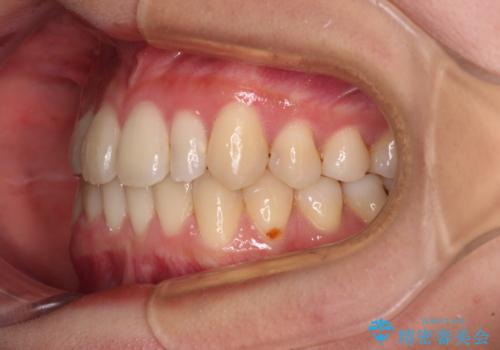

八重歯の抜歯矯正 補助装置を用いたインビザライン矯正

- 上顎の重なっている前歯を気にして来院された患者様です。

重なっている部分は抜歯が必要で、歯の移動量が多く、更には右側にずれている正中を改善する必要がありました。

インビザライン単体での治療は困難と判断し、補助装置により八重歯移動後にインビザラインを用いることとしました。

非常にしっかりとマウスピースを装着してくださいましたが、前歯の排列がなかなか仕上がらずに期間がかかってしまいました。